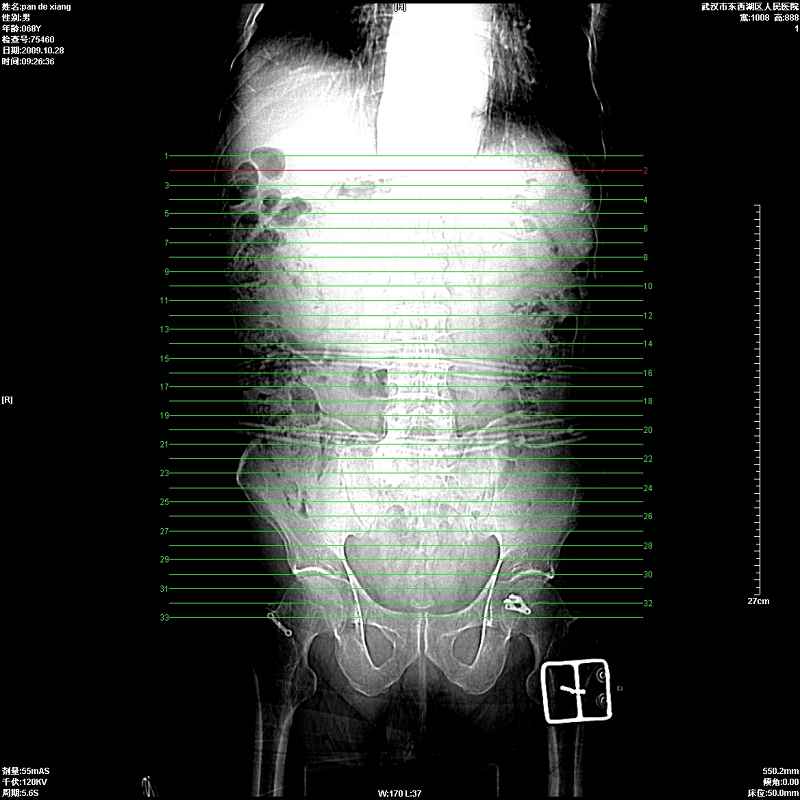

以下是引用杀毒软件在2009-10-28 20:41:00的发言:[br]结合临床考虑---白血病双肾改变或淋巴瘤。

以下是引用zxl51642在2009-10-29 9:59:00的发言:[br]结合临床“单克隆免疫球蛋白血症”,考虑双肾为继发损害并肾功能不全(尿中大量igg及少量iga、igm等大分子免疫球蛋白滤出所致继发损害),椎前软组织肿块为髓外造血。与浆细胞瘤有区别,平扫时有战友说的很清楚。